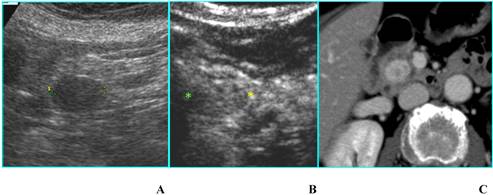

Serous microcystic adenoma in an asymptomatic 82-year-old woman. A. B-mode US shows a focal lesion located in the head of the pancreas with a honeycomb appearance. Superior mesenteric artery (arrow) is visible. B. CEUS confirms the findings of B-mode US, allowing a better diagnostic confidence.

a) B-mode US can characterize a SMA when it demonstrates the typical honeycomb appearance [10,12]; CEUS, by depicting septa enhancement and the absence of papillary projections, allows a better diagnostic confidence (Fig. 5). In case of small nonsurgical lesions, CEUS doesn't need a further diagnostic step with CT and/or MR.

Fig 6

Benign mucinous cystic neoplasm in a 79 old-woman with history of abdominal pain. A. B-mode US shows a unilocular cyst 3,5 cm in diameter (asterisk), located in the uncinate process of the pancreas; main pancreatic duct, not dilated (white arrow), is visible. B. CEUS image confirms the unilocular aspect of the cyst (asterisk), without septa or mural nodules. C and D. MDCT confirms on axial image (C) the unilocular aspect of the cyst (asterisk) and on MinIP image (D) demonstrates the absence of communication with the pancreatic duct (black arrow); dilated bile duct (white arrow) is visible.

b) Unilocular single cyst (without internal septa, solid component, parietal or central calcifications) at B-mode US can be referred to pseudocyst, oligocystic serous cystadenoma, MCN, IPMT (branch-duct type) [12]; CEUS doesn't give any additional diagnostic information (Figs. 6A and B): in particular it is not able to find out communication with the pancreatic duct that can be demonstrated by MR cholangiopancreatography or CT, especially with curved reformatted images (Figs. 6C and D), in IPMTs [13].